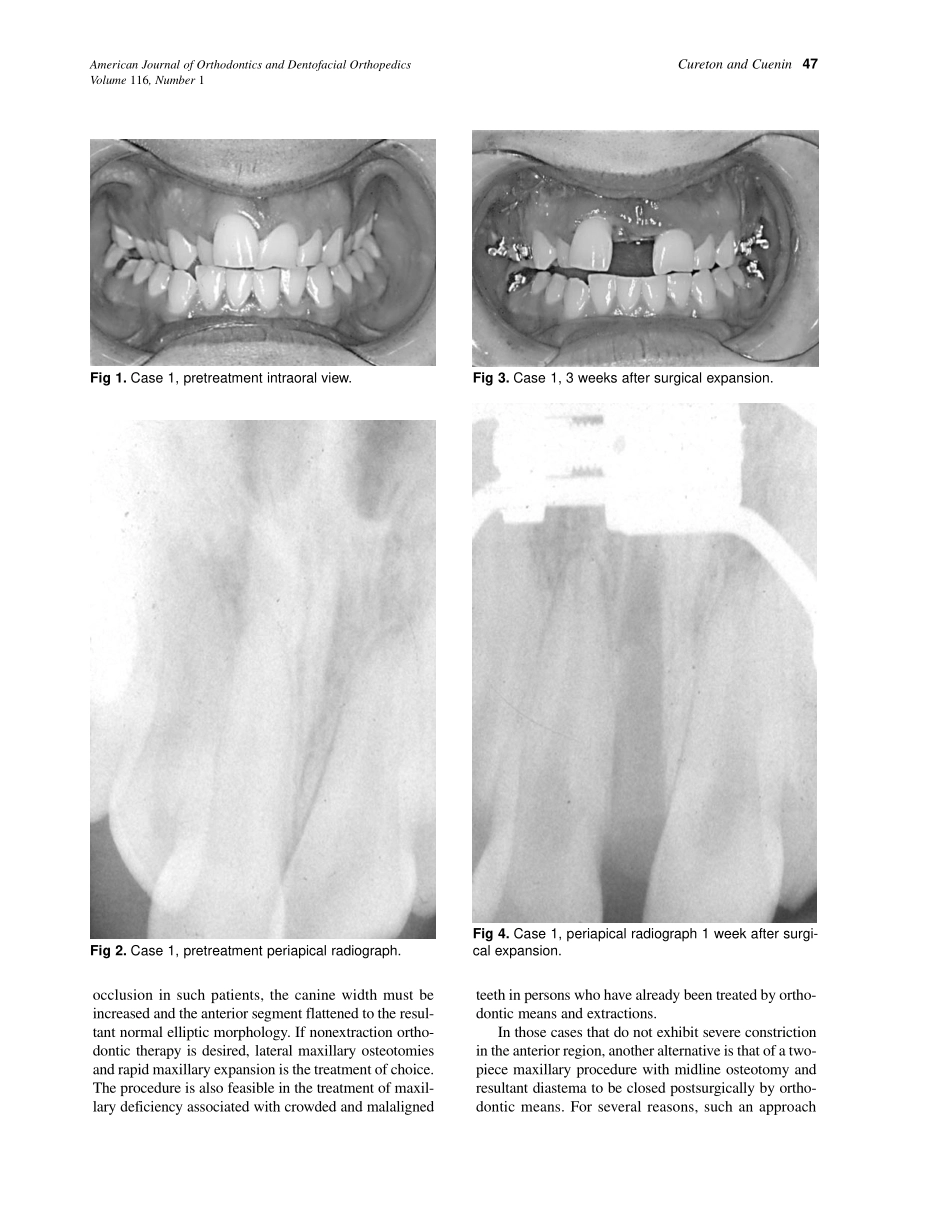

46Nonsurgicalrapidpalatalexpansion(RPE)wasusedbyAngle1asearlyas1860andcontinuestobeusedbyorthodontistswithahighrateofsuccessforgrowingchildren.AlthoughRPEhasbeenrelativelysuccessfulinchildrenandado...